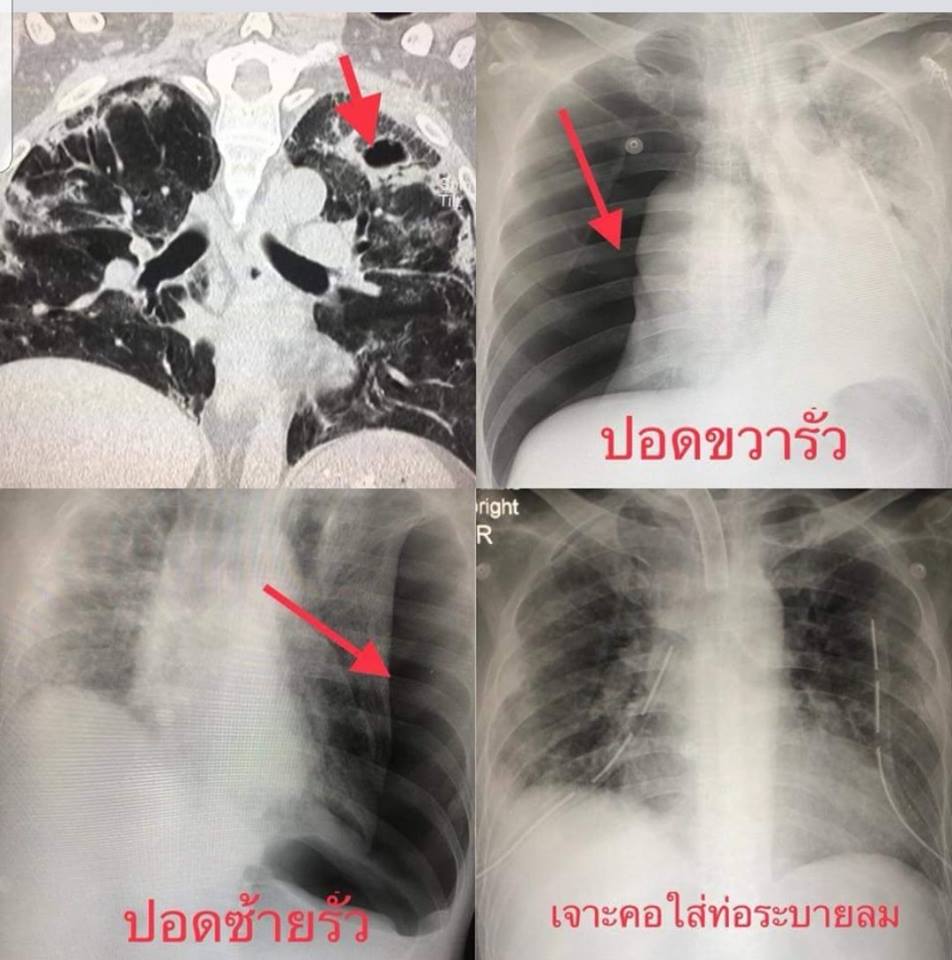

39937493_680148972345071_4164592412678684672_n.jpg

39933088_680148895678412_2185763046536773632_n.jpg

39973410_680149015678400_5798826807381721088_n.jpg